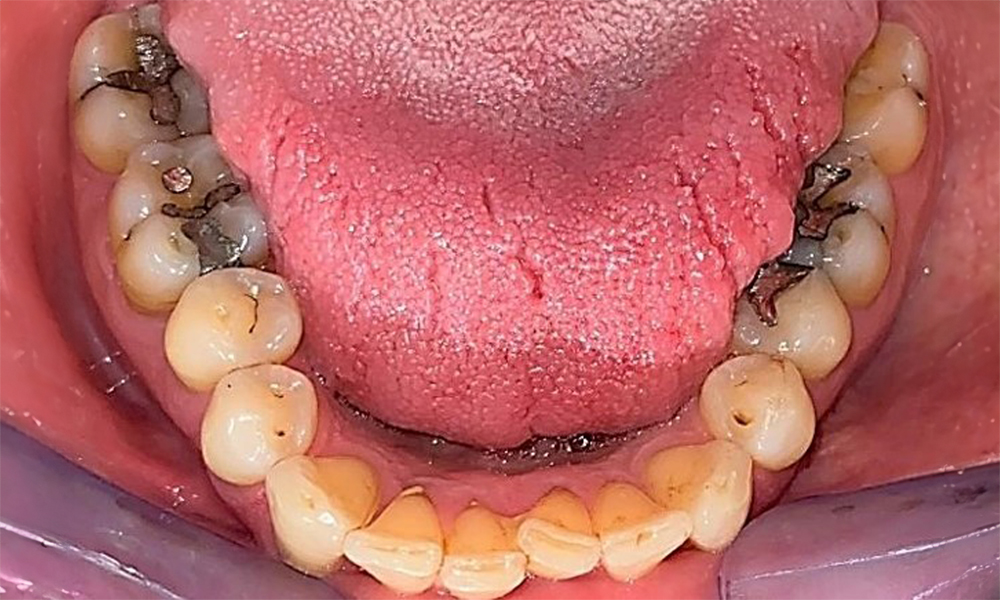

Occlusal view of the mandible showing the denture in situ.

Fig. 6 Occlusal view of the mandible showing the denture in situ. © Dr R. Krapf